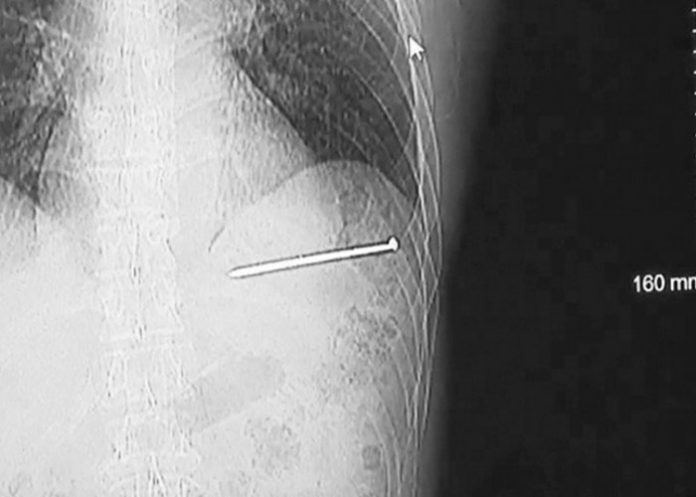

El estadounidense Doug Bergeson trabajaba en la chimenea de su vivienda de Wisconsin, en el norte del país, cuando sufrió un accidente que podría haberle costado la vida. Una pistola de clavos se disparó por accidente y le ocasionó una grave lesión cardíaca, publicó el sitio del canal WBAY TV.

Aunque primero pensó que los clavos solo le habían "rozado", al ver que uno incrustado en su pecho se movía con cada latido del corazón pensó: "Esto no es bueno". Entonces, se lavó la sangre y, como estaba solo en su casa, subió a su vehículo y manejó algo más de 19 kilómetros hasta el hospital.

Ya en el hospital, mientras era examinado, avisó de lo sucedido a su esposa y, posteriormente, fue trasladado hasta otro centro médico para ser intervenido. La cirugía ha sido exitosa y Bergeson solo ha perdido una arteria, aunque los médicos advirtieron de que si el clavo le hubiese penetrado en otra posición podría haber acabado con su vida.